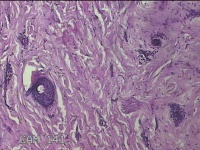

右前臂纹身

性别

男

年龄

22岁

临床诊断

纹身

一般病史

右前臂纹身切除。

标本名称

大体所见

灰白粉红色皮肤样组织6.5x0.8x0.3cm一块,表面糜烂,切面灰白粉红色,质软。

图2

慢性炎,瘢痕组织增生。